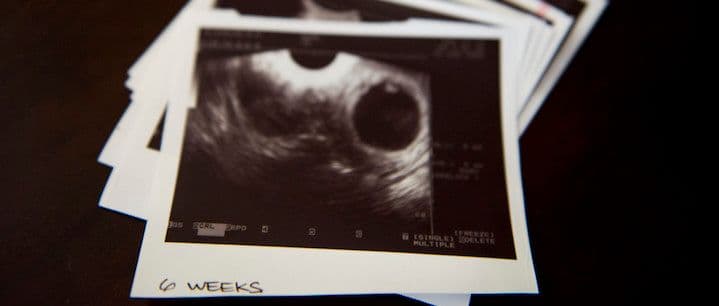

The first trimester of the pregnancy brings about the most dramatic changes. Our 12 step program helps you survive this important trimester